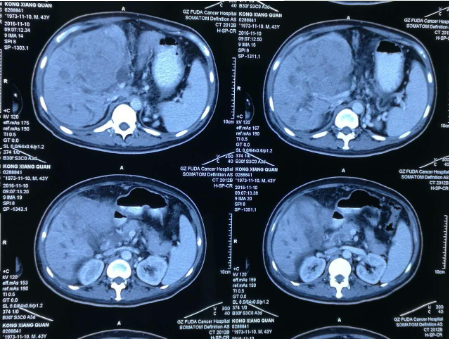

孔祥泉,男性,43岁,因皮肤发黄、肝区不适一个月,各种检查结果很不乐观。MR检查见:“S4/8肝内多发结节及团块(最大102mm*81mm),考虑肝癌合并子灶,侵犯肝门区胆管,门静脉主干及分支、肝右静脉受压、管腔变窄,肝内胆管扩张。胆囊增大并壁周水肿。肝硬化、脾大、少量腹水,食管下段、胃底及脾周静脉曲张,肝门区、门腔间隙及腹主动脉旁淋巴结(百度搜索:广州复大肿瘤医院)。

看到检查结果,医生也不难理解中山大学附属医院为何做出那样的诊断。在面对这个正当年且重症的晚期肝癌病人,徐院长的眼神里满是同情与惋惜。

看了孔祥泉的片子和化验检查结果,教授心里很沉重,他说:“我要想办法救你先生,他太年轻了!”徐院长想用当今最先进携药微球介入治疗方法,是副作用最小的血管介入疗法,目前的情况做不了其他的治疗,建议先住院。